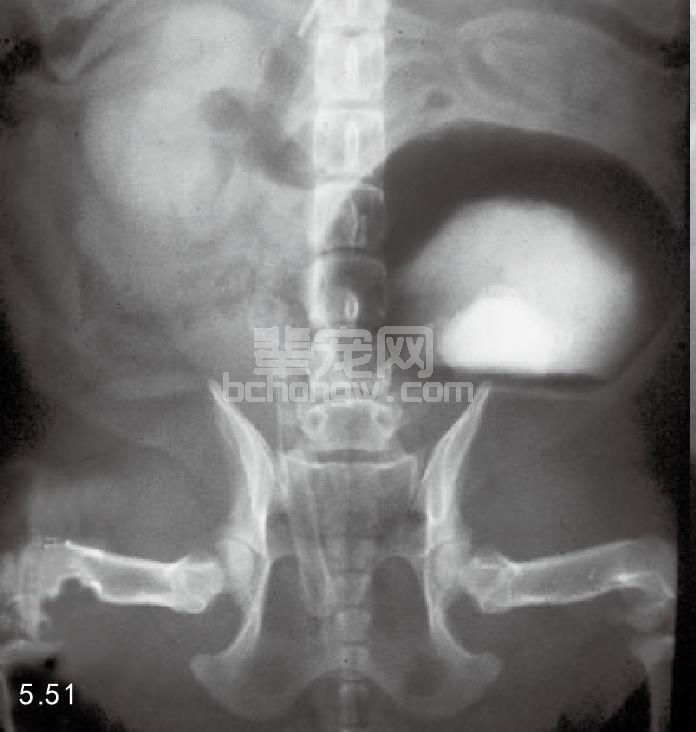

诊断 尿液分析对尿液沉积物做细胞学检查时很难发现肿瘤细胞,用生理盐水冲洗膀胱做细胞检查更可靠。 直接的组织抽吸也能获得准确的细胞学检查结果(图5.48)。X线片通常没有太大的价值,但是造影检查包括双 重造影和逆行性尿道造影可以显示充盈性缺陷,这些缺陷出现在正常光滑的造影剂药物膜的表面(图5.49~图 5.52)。超声在细针抽吸体内液体的帮助下也有助于诊断(图5.53)。

图5.51 犬移行性细胞癌的膀胱双重造影:腹背位观双重影像具有肿瘤密度显示,因为团块在阳性造影剂上面,未取代其位置。